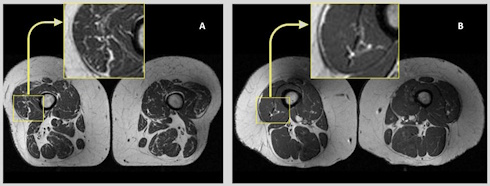

The MRI scan above on the left [click on the figure for a larger version] shows the leg muscles of an obese 58-year-old woman [A]. Her diet consisted of 68 percent ultra-processed foods.

The leg muscles of an obese 62-year-old woman [B] are shown on the top right. Her diet consisted of 'only' 36 percent ultra processed foods. As you can see, the leg muscles of woman B contain demonstrably less fat tissue than the muscles of woman A.